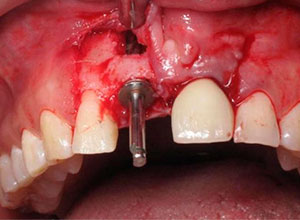

Después de la corticotomia dejamos un tiempo de siete días para que se organizaran las células tisulares.

Se empezó a hacer la distracción, primero con un arco recto y posteriormente con elásticos haciendo el recorte con el borde incisal conforme se va bajando el implante con el bloque óseo.

Al término de la distracción dejamos pasar tres meses con una férula en acrílico. En el diente 21 que habíamos visto en la radiografía un problema de un absceso periapical y periodontal.